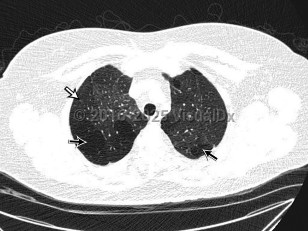

The clinical syndrome manifests as an airway obstruction, cough, and slowly progressive dyspnea (weeks to months), with radiographic examination showing normal or hyperinflation of the lungs. Tachypnea, crackles, and/or wheezing may be evident on physical examination.